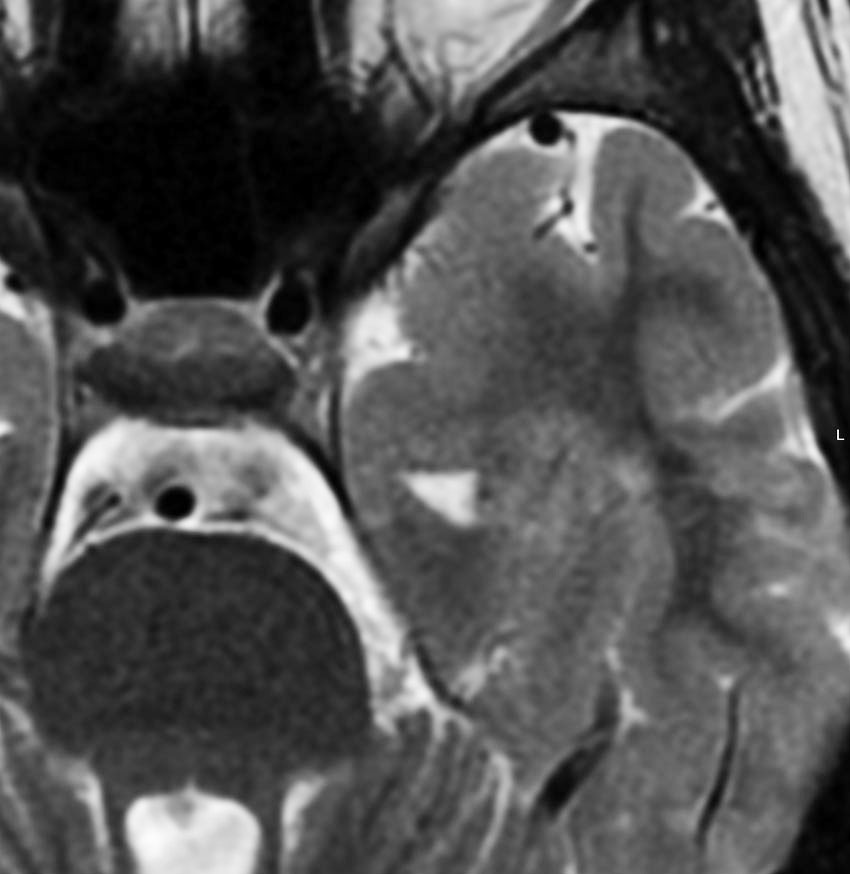

60代の女性に無症候で発見された稀な部位のPXA。結節様ですが脳とのはっきりした境はなく,多房性ののう胞を伴っていました。T2とFLAIR像ではわずかな浸潤像あるいは腫瘍周辺浮腫が疑われます。PXAに特徴的な画像ですが,大脳深部発生でもあり,PXAと画像診断することはできません。定位脳生検術 MRI-guided sterotactic biopsyで病理組織診断を行ない経過観察しました。

3年観察したら嚢胞を伴って増大しました。幸いのう胞性拡大が脳表方向であったのでparietal transcortical approachで全摘出できました。側脳室三角部腫瘍への到達法と同じアプローチですが,この経路では頭頂葉症候を後遺することがありません。